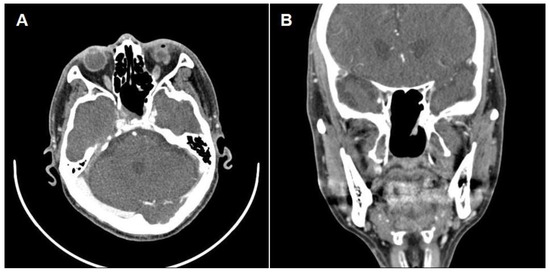

2. Case Report